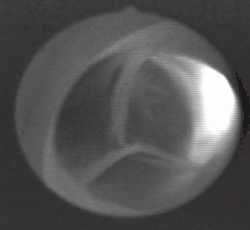

The aortic valve is a valve in the heart of humans and most other animals, located between the left ventricle and the aorta. It is one of the four valves of the heart and one of the two semilunar valves, the other being the pulmonary valve. The aortic valve normally has three cusps or leaflets, although in 1–2% of the population it is found to congenitally have two leaflets.[1] The aortic valve is the last structure in the heart the blood travels through before stopping the flow through the systemic circulation.[1]

The aortic valve normally has three cusps however there is some discrepancy in their naming.[2] They may be called the left coronary, right coronary and non-coronary cusp.[2] Some sources also advocate they be named as a left, right and posterior cusp.[3][4] Anatomists have traditionally named them the left posterior (origin of left coronary), anterior (origin of the right coronary) and right posterior.[2]

The three cusps, when the valve is closed, contain a sinus called an aortic sinus or sinus of Valsalva. In two of these cusps, the origin of the coronary arteries are found. The width of the sinuses in cross-section is wider than the left ventricular outflow tract as well as wider than the ascending aorta. The junction of the sinuses with the aorta is called the sinotubular junction. The aortic valve is located posterior to the pulmonary valve and the commissure where the anterior two cusps join together points toward the pulmonary valve. It is these two sinuses that contain the origin of the coronary arteries. In the congenital disease known as transposition of the great arteries, these two valves are reversed (the anterior valve is the aortic valve) and the origin of the coronaries still follows this "rule" that the origins are in the sinuses facing the pulmonary valve.

The term "semilunar" refers to an approximate half-moon shape of the valve leaflets.[5]